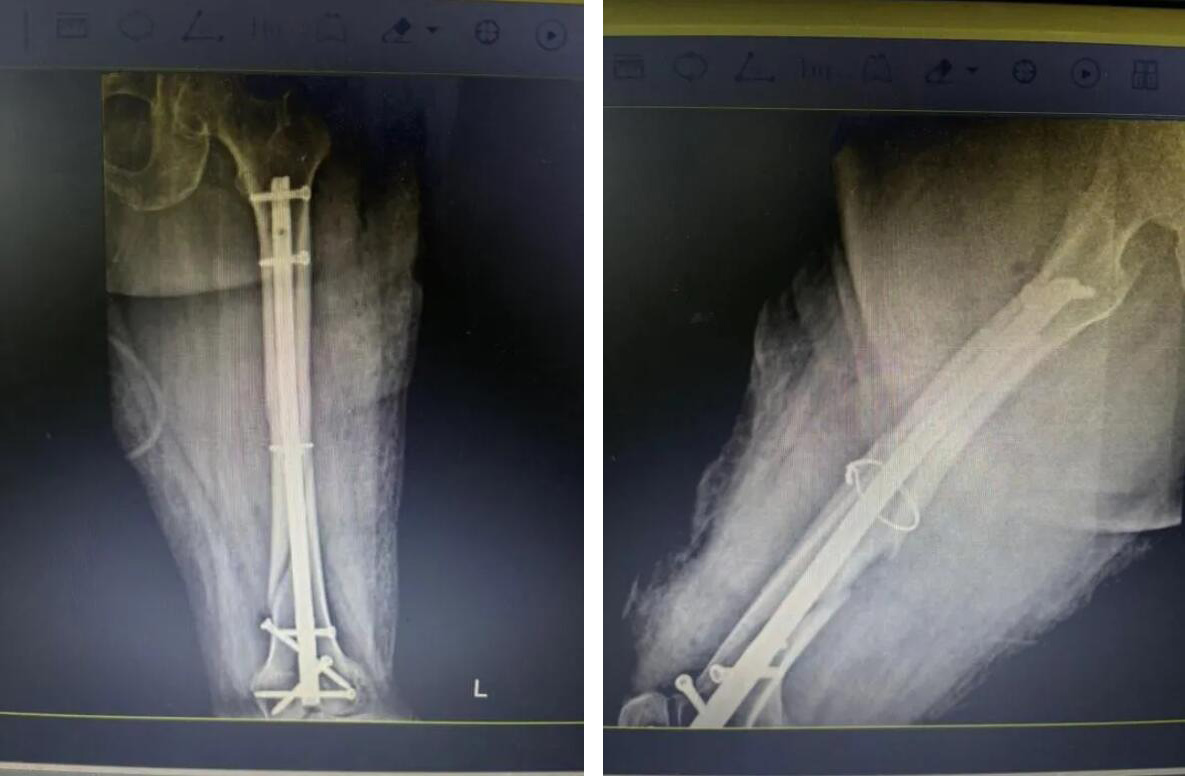

近日,我院關(guān)節(jié)科羅軍副院長團隊成功為一位95歲高齡的俞奶奶實施了“股骨多段骨折閉合復位微創(chuàng)內(nèi)固定術(shù)”,憑借精湛的技術(shù)和先進的微創(chuàng)理念,成功闖過“超高齡”手術(shù)禁區(qū)。

術(shù)后,俞奶奶恢復情況良好,可自行在助行器輔助下緩慢行走。這一手術(shù)的成功,標志著我院在老年創(chuàng)傷骨科領(lǐng)域的救治水平達到了新的高度。

經(jīng)過充分準備,醫(yī)療團隊決定為俞奶奶實施 “閉合復位微創(chuàng)內(nèi)固定術(shù)”。

與傳統(tǒng)開放手術(shù)不同,醫(yī)生不在骨折處做長切口,而是通過幾個僅1-2厘米的“鑰匙孔”小切口,在C型臂X光機的精準導航下,將骨折斷端巧妙地對合復位,然后植入髓內(nèi)釘進行堅固固定。

手術(shù)歷時約一小時,過程非常順利。術(shù)中出血量極少,最大程度減少了對患者生理機能的干擾。